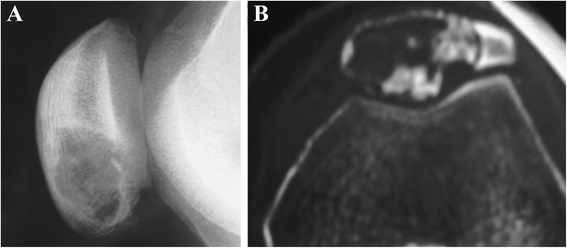

The patella is an uncommon location for cancerous occurrence and development. The majority of tumors of the patella are benign, with a significant incidence of giant cell tumors and chondroblastoma. With the development of modern diagnostic technologies, there appear however many other histological types which raise challenges of diagnosis and treatment. In this article, we review the reported histological types of primary patellar tumors. Specifically, epidemiology, symptomatology, imageology, histopathology, and treatment options for these histological lesions will be discussed, respectively. As there is an increasing focus on the diagnosis and the treatment of these lesions, the availability of the integrated information about primary patellar tumors becomes more significant.